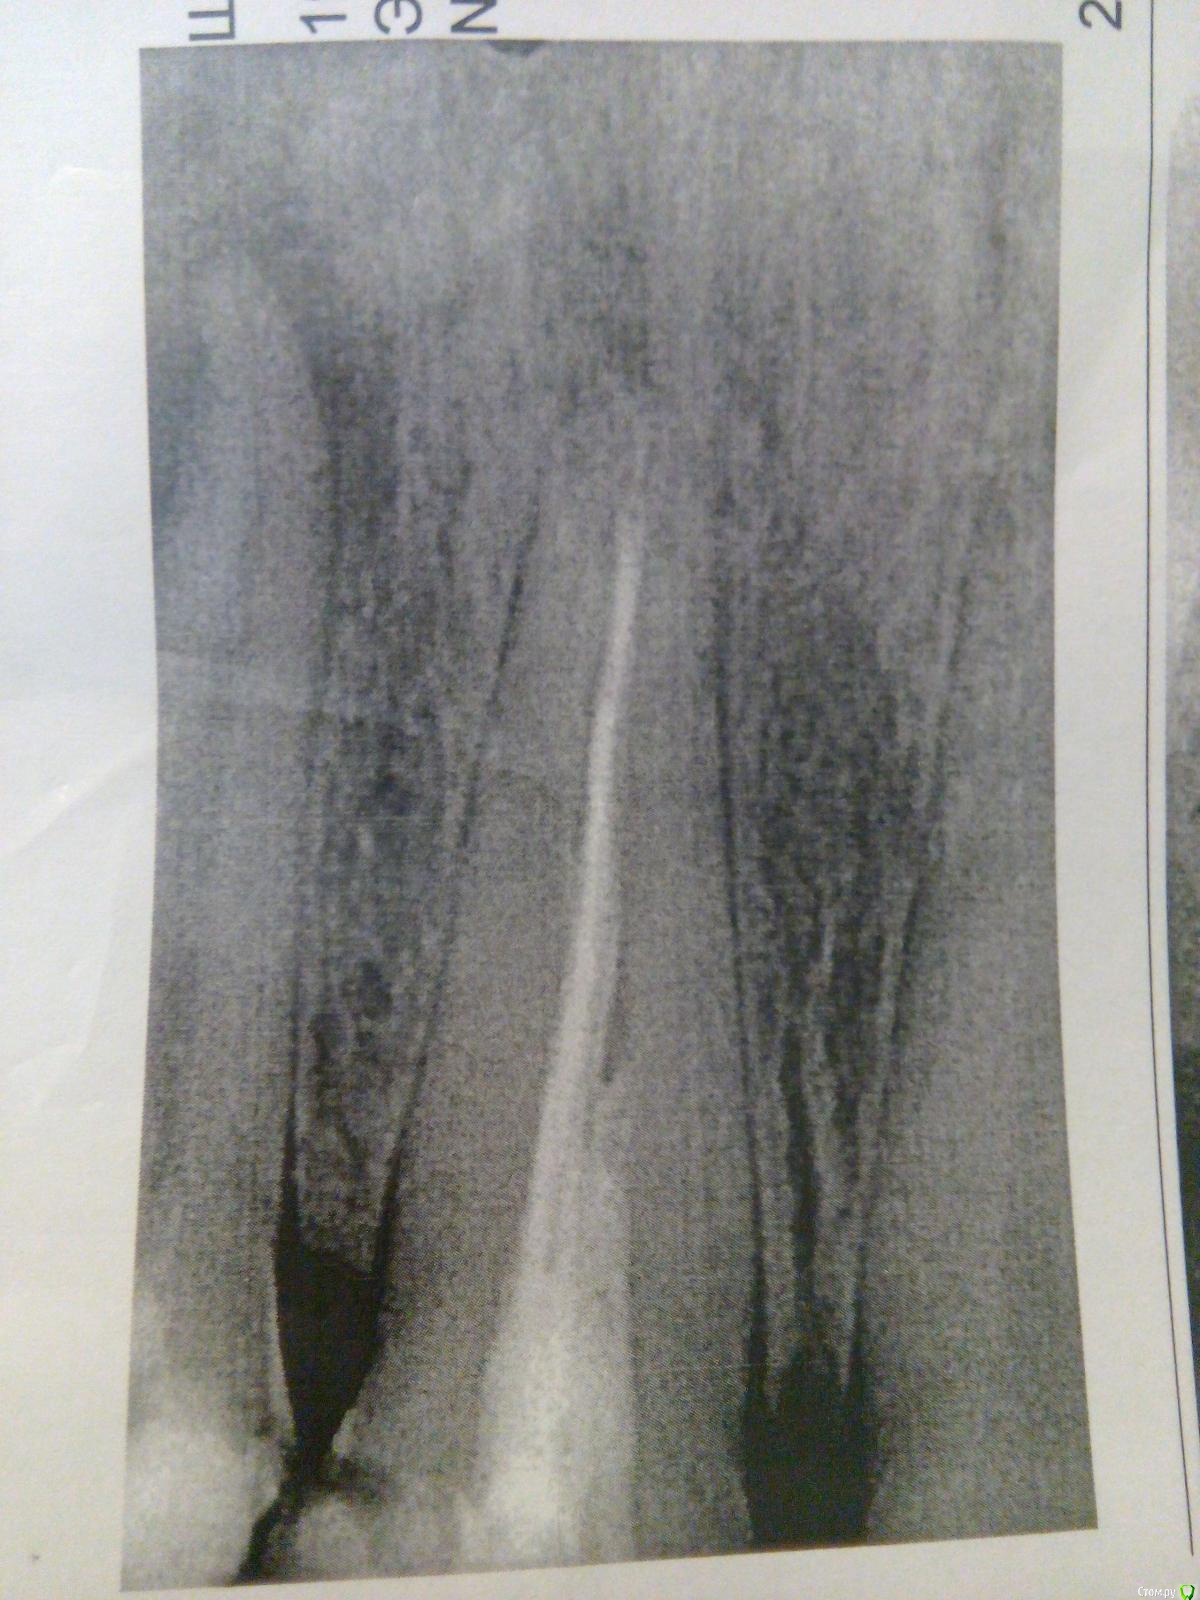

swansea Опубликовано 22 июля, 2016 Поделиться Опубликовано 22 июля, 2016 На единице стоит здоровая пломба: зуб пережил флюс и последующее лечение с прочисткой каналов. Врач сказал, что нужно распломбировывать соседний зуб, поскольку флюс был от него, там не запломбированы каналы. А виновник рентгена - ну, перепломбировать его. Но рядом стоящий надо лечить очень срочно, иначе возникнет вероятность его потерять. Меня, собственно, интересуют оба зуба. Я собираюсь лечить оба, просто вопрос в срочности лечения и с какого начать. Ссылка на комментарий

swansea Опубликовано 22 июля, 2016 Автор Поделиться Опубликовано 22 июля, 2016 Они оба не беспокоят. Вообще. В последний раз беспокоил тот, что с флюсом, хотя врач меня уверял, что на снимке ничего такого не видно, и флюс был на другом. Оправданы ли мрачные прогнозы о потере зуба с "таким воспалением на корне, вам нужно будет все промывать, проводить резекцию верхушки корня, каналы промывать долго"? Ссылка на комментарий